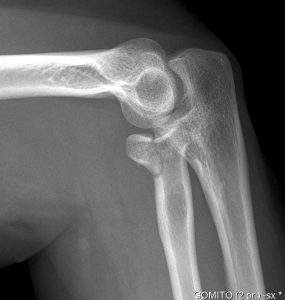

Nel caso in cui si abbia avuto un trauma o una caduta con conseguente dolore al gomito, il consiglio è quello di eseguire una radiografia per mostrare la presenza di una frattura.

In questo tipo di trauma l’esame attraverso raggi x risulta essere l’esame più indicato per mostrare la presenza di rime di frattura e vedere se sono presenti dei frammenti ossei che si sono staccati; la Risonanza magnetica invece viene suggerita solo nel caso siano presenti dei danni ai legamenti e alla capsula.

Nei casi gravi di frattura capitello radiale può essere utile una scansione sui vari piani per individuare bene anche il trattamento chirurgico da eseguire.